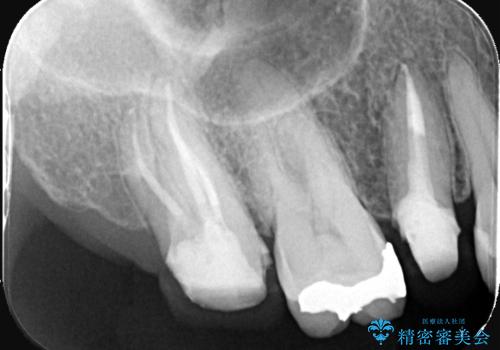

- 左上7番の奥歯に、根尖部の大きな病変を認め来院されました。レントゲンと精密検査の結果、歯の根の先に膿が溜まっている状態と診断。歯を残すことを第一に考え、精密根管治療による改善を目指す治療計画を立案しました。治療においては、細菌の侵入を徹底的に防ぎ、病変部を確実に除去するために、ラバーダムと歯科用顕微鏡を併用することを提案しました。

今回の精密根管治療では、まず治療中に唾液や細菌が入らないようラバーダムで患部を隔離しました。次に、肉眼では見えない根管内部を歯科用顕微鏡で拡大しながら確認。これにより、病変部を正確に特定し、感染源を徹底的に除去することができました。また、健康な歯質を極力残すため、必要以上に歯を削らないよう細心の注意を払って治療を進めました。治療後は、根尖部の病変がきれいになくなり、良好な経過をたどっています。これにより、大切な奥歯を残し、再感染のリスクを抑えることができました。